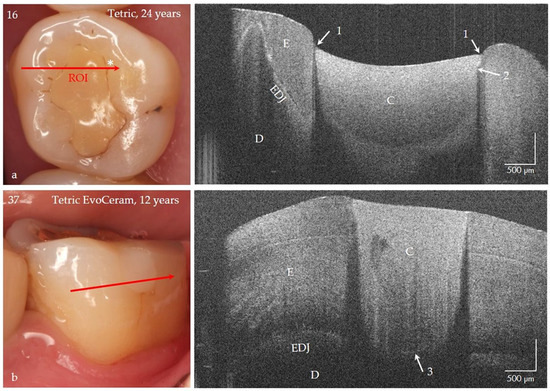

Caries, the world’s most common chronic disease, remains a major cause of invasive restorative dental treatment. To take advantage of the diagnostic potential of optical coherence tomography (OCT) in contemporary dental prevention and treatment, an intraorally applicable spectral-domain OCT probe has been developed based on an OCT hand-held scanner equipped with a rigid 90°-optics endoscope. The probe was verified in vitro. In vivo, all tooth surfaces could be imaged with the OCT probe, except the vestibular surfaces of third molars and the proximal surface sections of molars within a "blind spot" at a distance greater than 2.5 mm from the tooth surface. Proximal surfaces of 64 posterior teeth of four volunteers were assessed by intraoral OCT, visual-tactile inspection, bitewing radiography and fiber-optic transillumination. The agreement in detecting healthy and carious surfaces varied greatly between OCT and established methods (18.2–94.7%), whereby the established methods could always be supplemented by OCT. Direct and indirect composite and ceramic restorations with inherent imperfections and failures of the tooth-restoration bond were imaged and qualitatively evaluated. The intraoral OCT probe proved to be a powerful technological approach for the non-invasive imaging of healthy and carious hard tooth tissues and gingiva as well as tooth-colored restorations. Full article

Figure 1